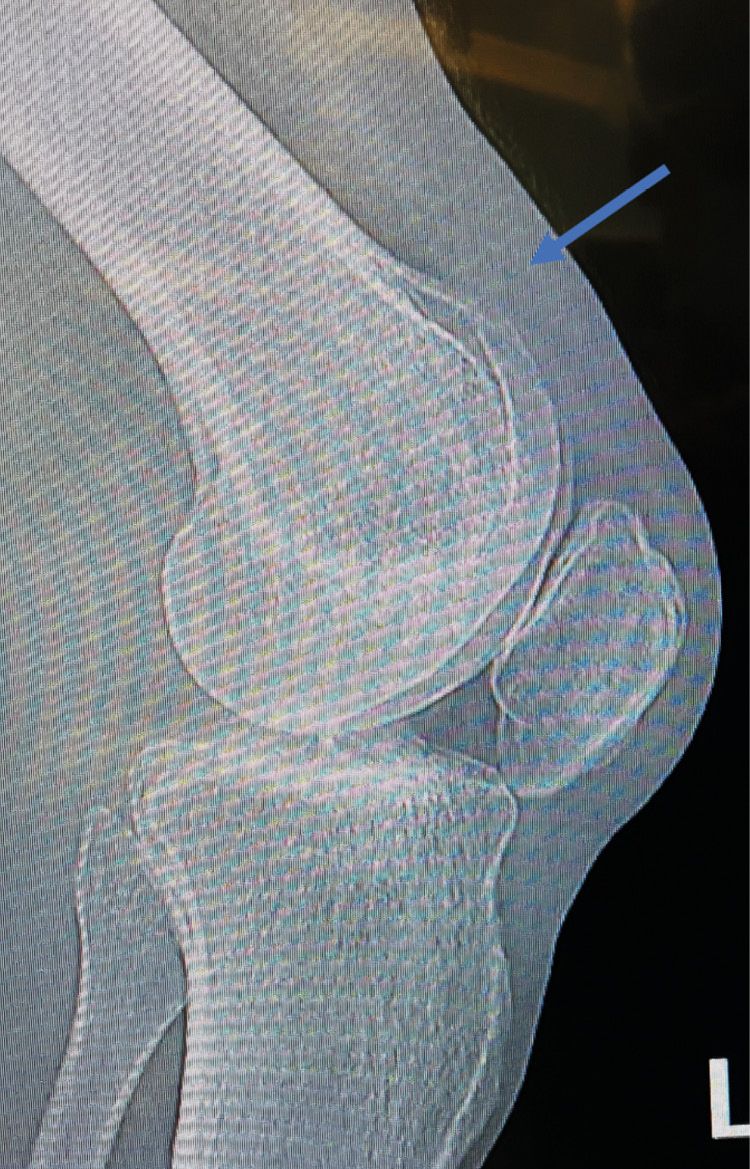

A strict lateral x-ray will help the diagnosis by revealing signs of pre-existing tendinopathy or a low-riding baja.[6] Siwek CW, Rao JP. Ruptures of the extensor mechanism of the knee joint. J Bone Joint Surg Am. 1981;63(6):932-937. The existence of a suprapatellar mass will sometimes indicate and help evaluate the tendon retraction (Fig. 2).